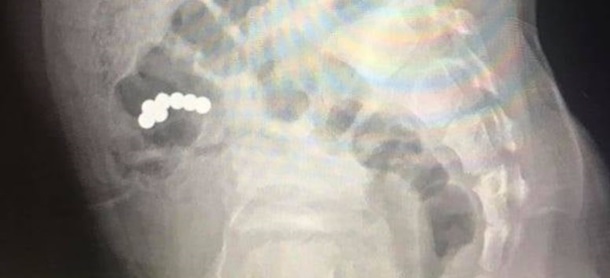

Під час рентгенологічного дослідження діагностували наявність магнітів у кишечнику. Предмети не просувалися 10 днів. Це стало показанням для оперативного хірургічного втручання.

Під час операції хірурги виявили, що зрослися стінки тонкої кишки, де були чотири магніти, зі стінкою сліпої кишки, де були три магніти. Медики видалили предмети.